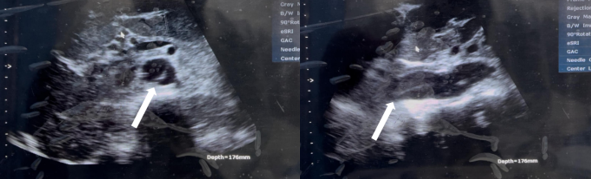

On arrival all vitals were unremarkable except for a BP: 147/87 mmHg, a HR: 123 bpm and a RR: 24 ppm. Secondary physical examination was also unremarkable. A Point-of-care ultrasound (POCUS) quickly revealed an abdominal aortic dissection as seen in the transverse (Figure 1a) and longitudinal (Figure 1b) views of the aorta.

Figure 1: POCUS images showing the abdominal aortic dissection in the transverse (Figure 1a: left) and longitudinal (Figure 1b: right) sub-xyphoid views of the aorta

The non-specific presentation of chest pain, often misdiagnosed as musculoskeletal or gastrointestinal issues, can delay the patient’s presentation. The use of POCUS in the emergency room proved its usefulness, providing rapid visualization of the abdominal dissection flap (Figures 1a and 1b) and prompting the definitive CT angiography. CT angiography remains the gold standard for diagnosis, determining the Stanford/DeBakey type, entry/re-entry tears, and, most critically, identifying malperfusion syndromes involving branch vessel ostia, which directly impacts management and surgical planning [4].